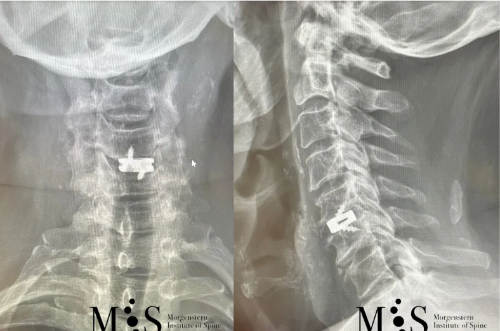

Ejemplo Caso Clínico

Esta paciente de 49 años con una hernia cervical migrada cranealmente en C4/C5 y una inestabilidad en C5/C6 se le realizó una fusión cervical en dos niveles poniendo dos cajas cervicales a través de una incisión en la piel de sólo 2 cm. La recuperación post-operatoria de la paciente fue excelente y muy rápida, pudiéndose dar el alta hospitalaria en menos de 24 horas después de la cirugía.